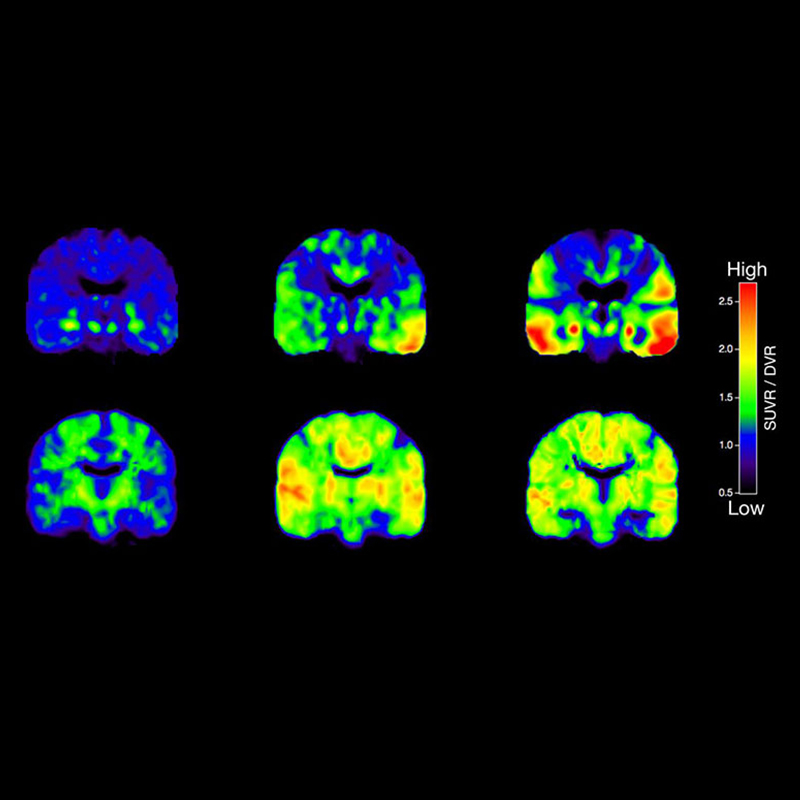

Beyin fonksiyonlarını (fMRI), doku metabolizmasını (MR spektroskopi) ve kan akışını değerlendirmek için uygundur.

İnme, tümörler, epilepsi, Alzheimer gibi nörolojik hastalıkların teşhis ve takibinde çok etkilidir.

o Beyin fonksiyonlarını (fMRI), doku metabolizmasını (MR spektroskopi) ve kan akışını değerlendirmek için uygundur.

o İnme, tümörler, epilepsi, Alzheimer gibi nörolojik hastalıkların teşhis ve takibinde çok etkilidir.